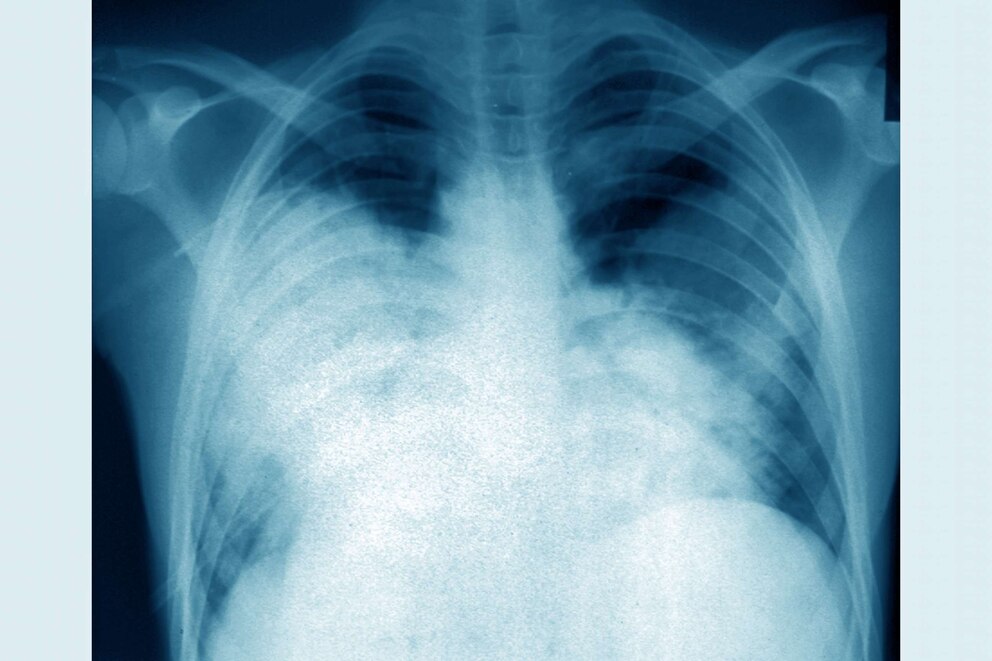

Legionnaires' is a severe form of pneumonia caused by inhaling the bacteria in small droplets of water or accidentally swallowing water containing Legionella.

According to the World Health Organization, the cases appeared between Aug. 18 and Aug. 25 with patients complaining of fever, muscle aches, abdominal pain and difficulty breathing along with pneumonia symptoms.